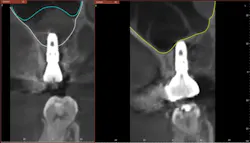

Hydraulic sinus lifting is a technological leap forward in sinus lift procedures. These innovative devices utilize hydraulic pressure to lift the sinus membrane gently and precisely, creating sufficient space for implant placement without the need for excessive bone manipulation (figure 3).

Hydraulic lifts can effectively prevent many of the aforementioned complications. Membrane perforations and injury to nearby vital structures are minimized because of the use of millimeter-precise drill stoppers, as well as simply using saline instead of blunt instruments to separate the thin sinus membrane. The flat-ended drills and stoppers in hydraulic techniques eliminate much of the guesswork involved in drilling to breach the sinus.

As the landscape of implantology evolves, the adoption of hydraulic lifts is poised to become the gold standard in noninvasive sinus lift surgeries, reshaping the future of dental implant procedures (figures 4–11).